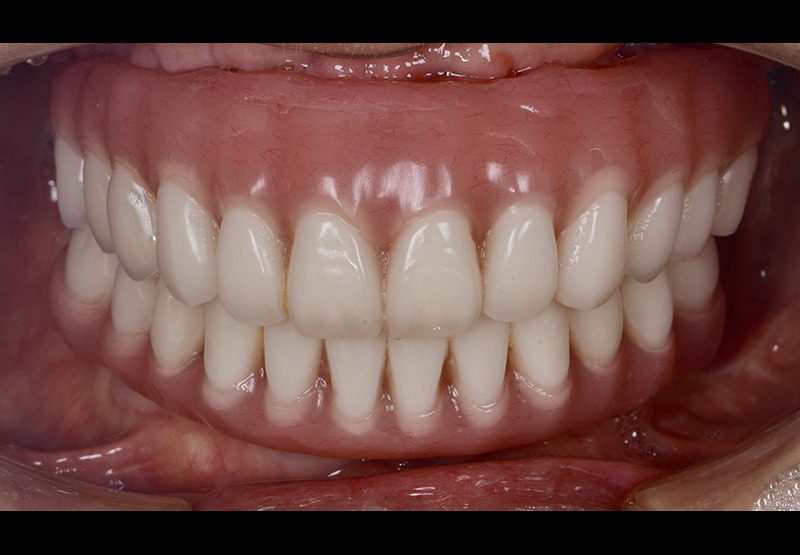

Final restration

口腔内(正面)

After

最終補綴装置は上下フルジルコニア上部構造で、傷が付かない、臭いが付かない最も整体親和性の高い素材です。当クリニックでは万が一の破折に備え全てのジルコニアにスペア(人工歯タイプ)を用意し、なるべく患者様にご迷惑がかからない治療を行なっております。